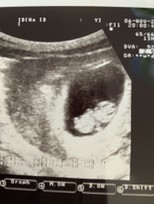

9 W

9 W เจอน้องกันยังคะแม่ๆ หมอบอกน้องยังตัวเล็กอยู่อาจจะไม่ค่อยชัดของแม่แต่ละบ้านเป็นงัยกันบ้างคะ